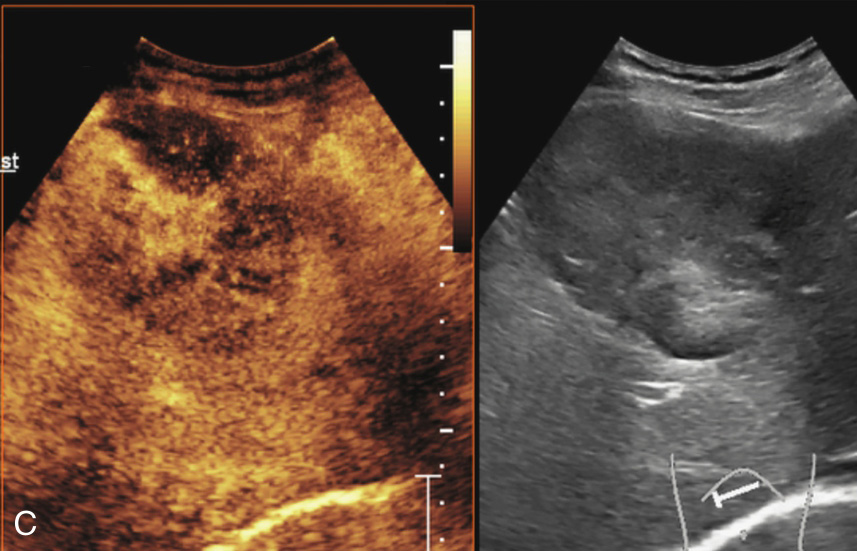

(5)超声造影:

动脉早期病灶呈周边环状增强或整体高增强,门脉早期病灶内造影剂消退呈低增强(图1-7-6)。

A.造影剂注入14s周边不规则环状增强;B.35s病灶内造影剂开始消退呈低增强

图1-7-6(续)

C、D.门脉期及延迟期造影剂持续消退呈低增强